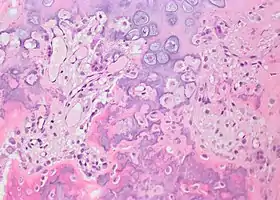

Histopathology

Bone Bizzare Parosteal Osteochondromatous Proliferation